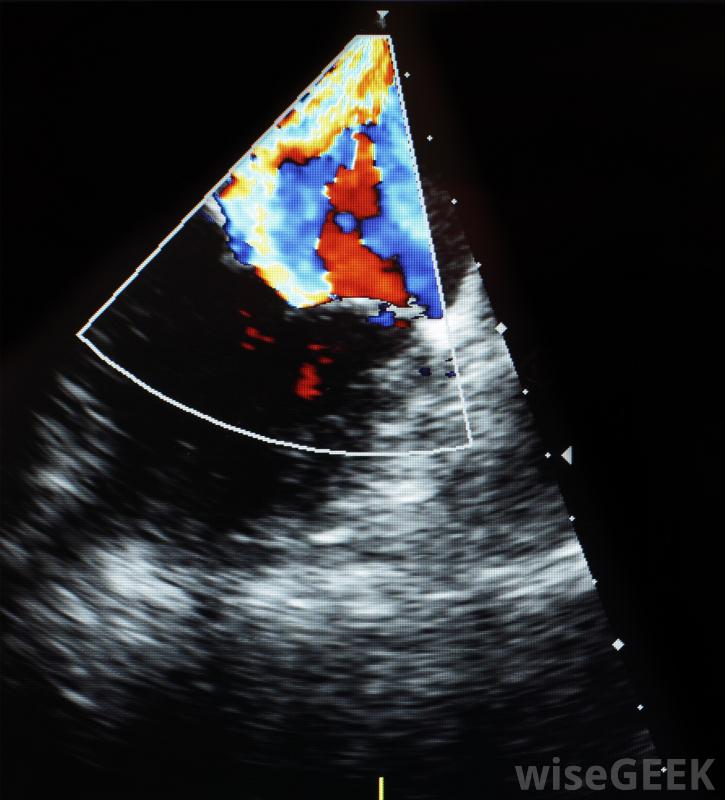

医用多普勒设备使用高频声波监测内脏。

医学领域使用数字多普勒来拯救生命。在这种情况下,电磁波被用来给医生一个身体内部的视觉表现,而不切割皮肤。这些波可以产生二维或三维视图指体内的器官或异物。妊娠超声利用二维和三维多普勒给父母和产科医生一张婴儿的第一张照片。